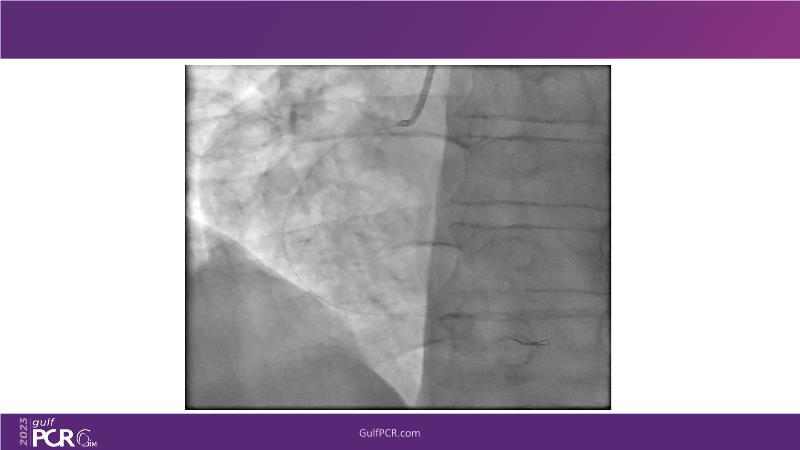

This session is a valuable resource for grasping innovative strategies in handling bifurcation and extended diffuse lesions through dedicated stenting solutions. Explore insights into the advanced Myval next-generation THV technology, unveiling its distinctive features, procedural advantages, and clinical outcomes across a diverse patient pool. Gain understanding into the CorAlign technique, ensuring accurate commissural and coronary alignment while maintaining coronary access. Additionally, delve into the techniques for precise sizing, positioning, and deploying of Myval THV.

- To learn about the novel Myval next generation THV technology, its key features, procedural and clinical benefits and learn about the clinical data in a vast cohort of patient population

- To understand the CorAlign technique which enables predictable and precise commissural and coronary alignment thus preserving coronary access